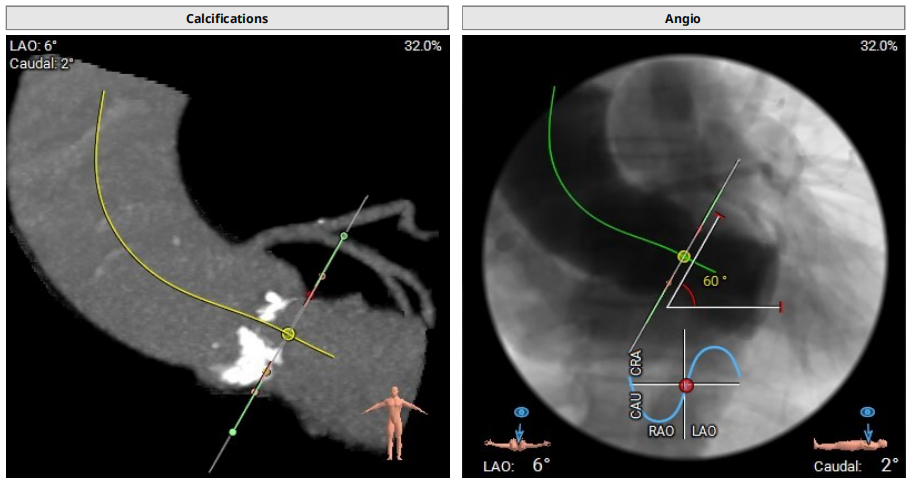

病例1:患者男性,70岁,三叶瓣。主动脉瓣重度狭窄,钙化集中于右冠窦、无冠窦,瓣环面积径23.3mm。左冠高度11.3mm,右冠高度16.1mm。外周入路可见钙化,内径尚可。

术中经右侧股动脉入路,使用19mm球囊预扩,顺利植入23# RENATUS®球扩式经导管主动脉瓣,瓣膜释放位置理想、形态及功能良好,无外周血管损伤,术后无瓣中及瓣周反流等并发症。

术前评估